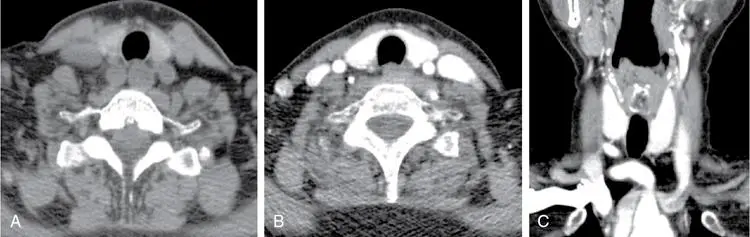

Normal CT appearance of the thyroid gland: (Source)

Non-contrast axial CT images (A) shows a normal hyperdense thyroid gland relative to the adjacent skeletal muscles. Contrast axial (B) and coronal (C) images shows intense enhancement of the thyroid gland.